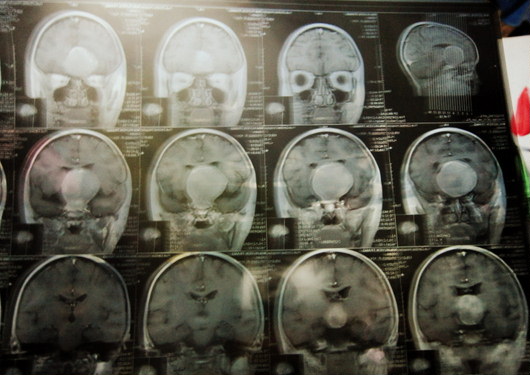

Chị Tôn Nữ Phương Mai, mẹ của bé xót xa cho biết: “Các bác sĩ hội chẩn cháu có khối u não rất to, đường kính tới 5 cm, chiếm 1/3 diện tích hộp sọ nên khối u chèn vào dây thần kinh khiến mắt cháu bị teo gai thị nặng và thêm các biến chứng khác”.